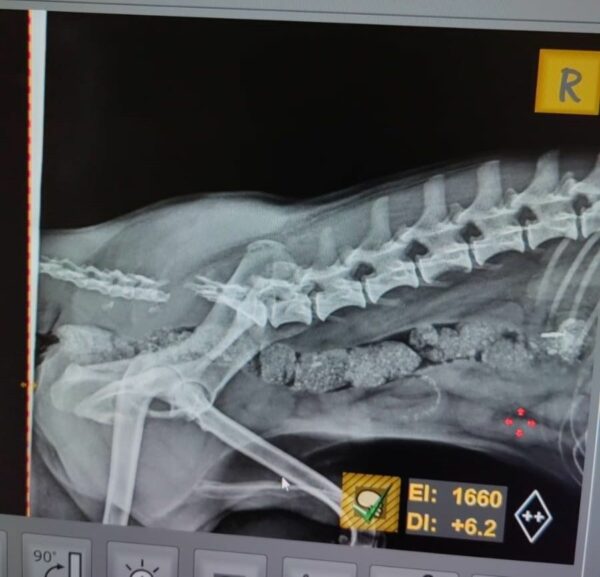

Unterschenkel-Bruch in Behandlung und amputierte Rute (10/2024)

Dieser kleine Rüde hat bereits einiges durchmachen müssen. PEANUT wurde mit einem gebrochenen Bein und einer gebrochenen Rute gefunden und befindet sich derzeit in der Klinik, wo das Beinchen bereits operiert wurde. Seine Rute musste leider, aufgrund der schweren Verletzung, amputiert werden. Trotz all dieser Herausforderungen ist der kleine PEANUT ein tapferer, lieber Kerl, der sich nichts mehr wünscht, als endlich ein warmes, sicheres Zuhause zu finden, in dem er sich erholen und geborgen fühlen kann. Wer schenkt PEANUT eine zweite Chance und zeigt ihm, wie schön das Leben sein kann?

| zur Besonderheit: | Amputierte Rute. Unterschenkel-Bruch in Behandlung |